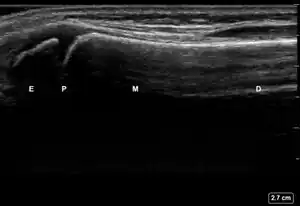

| 3 | Cortical Break Fracture | "Broken" | Break, step or gap in bone cortex which appears as a black zone in the bright, sharp white line[10][11][14][15][16] | ![]() Ultrasound dorsal view of cortical break fracture of radius (shown by arrow). E = epiphysis; P = physis; M = metaphysis; D = diaphysis. |